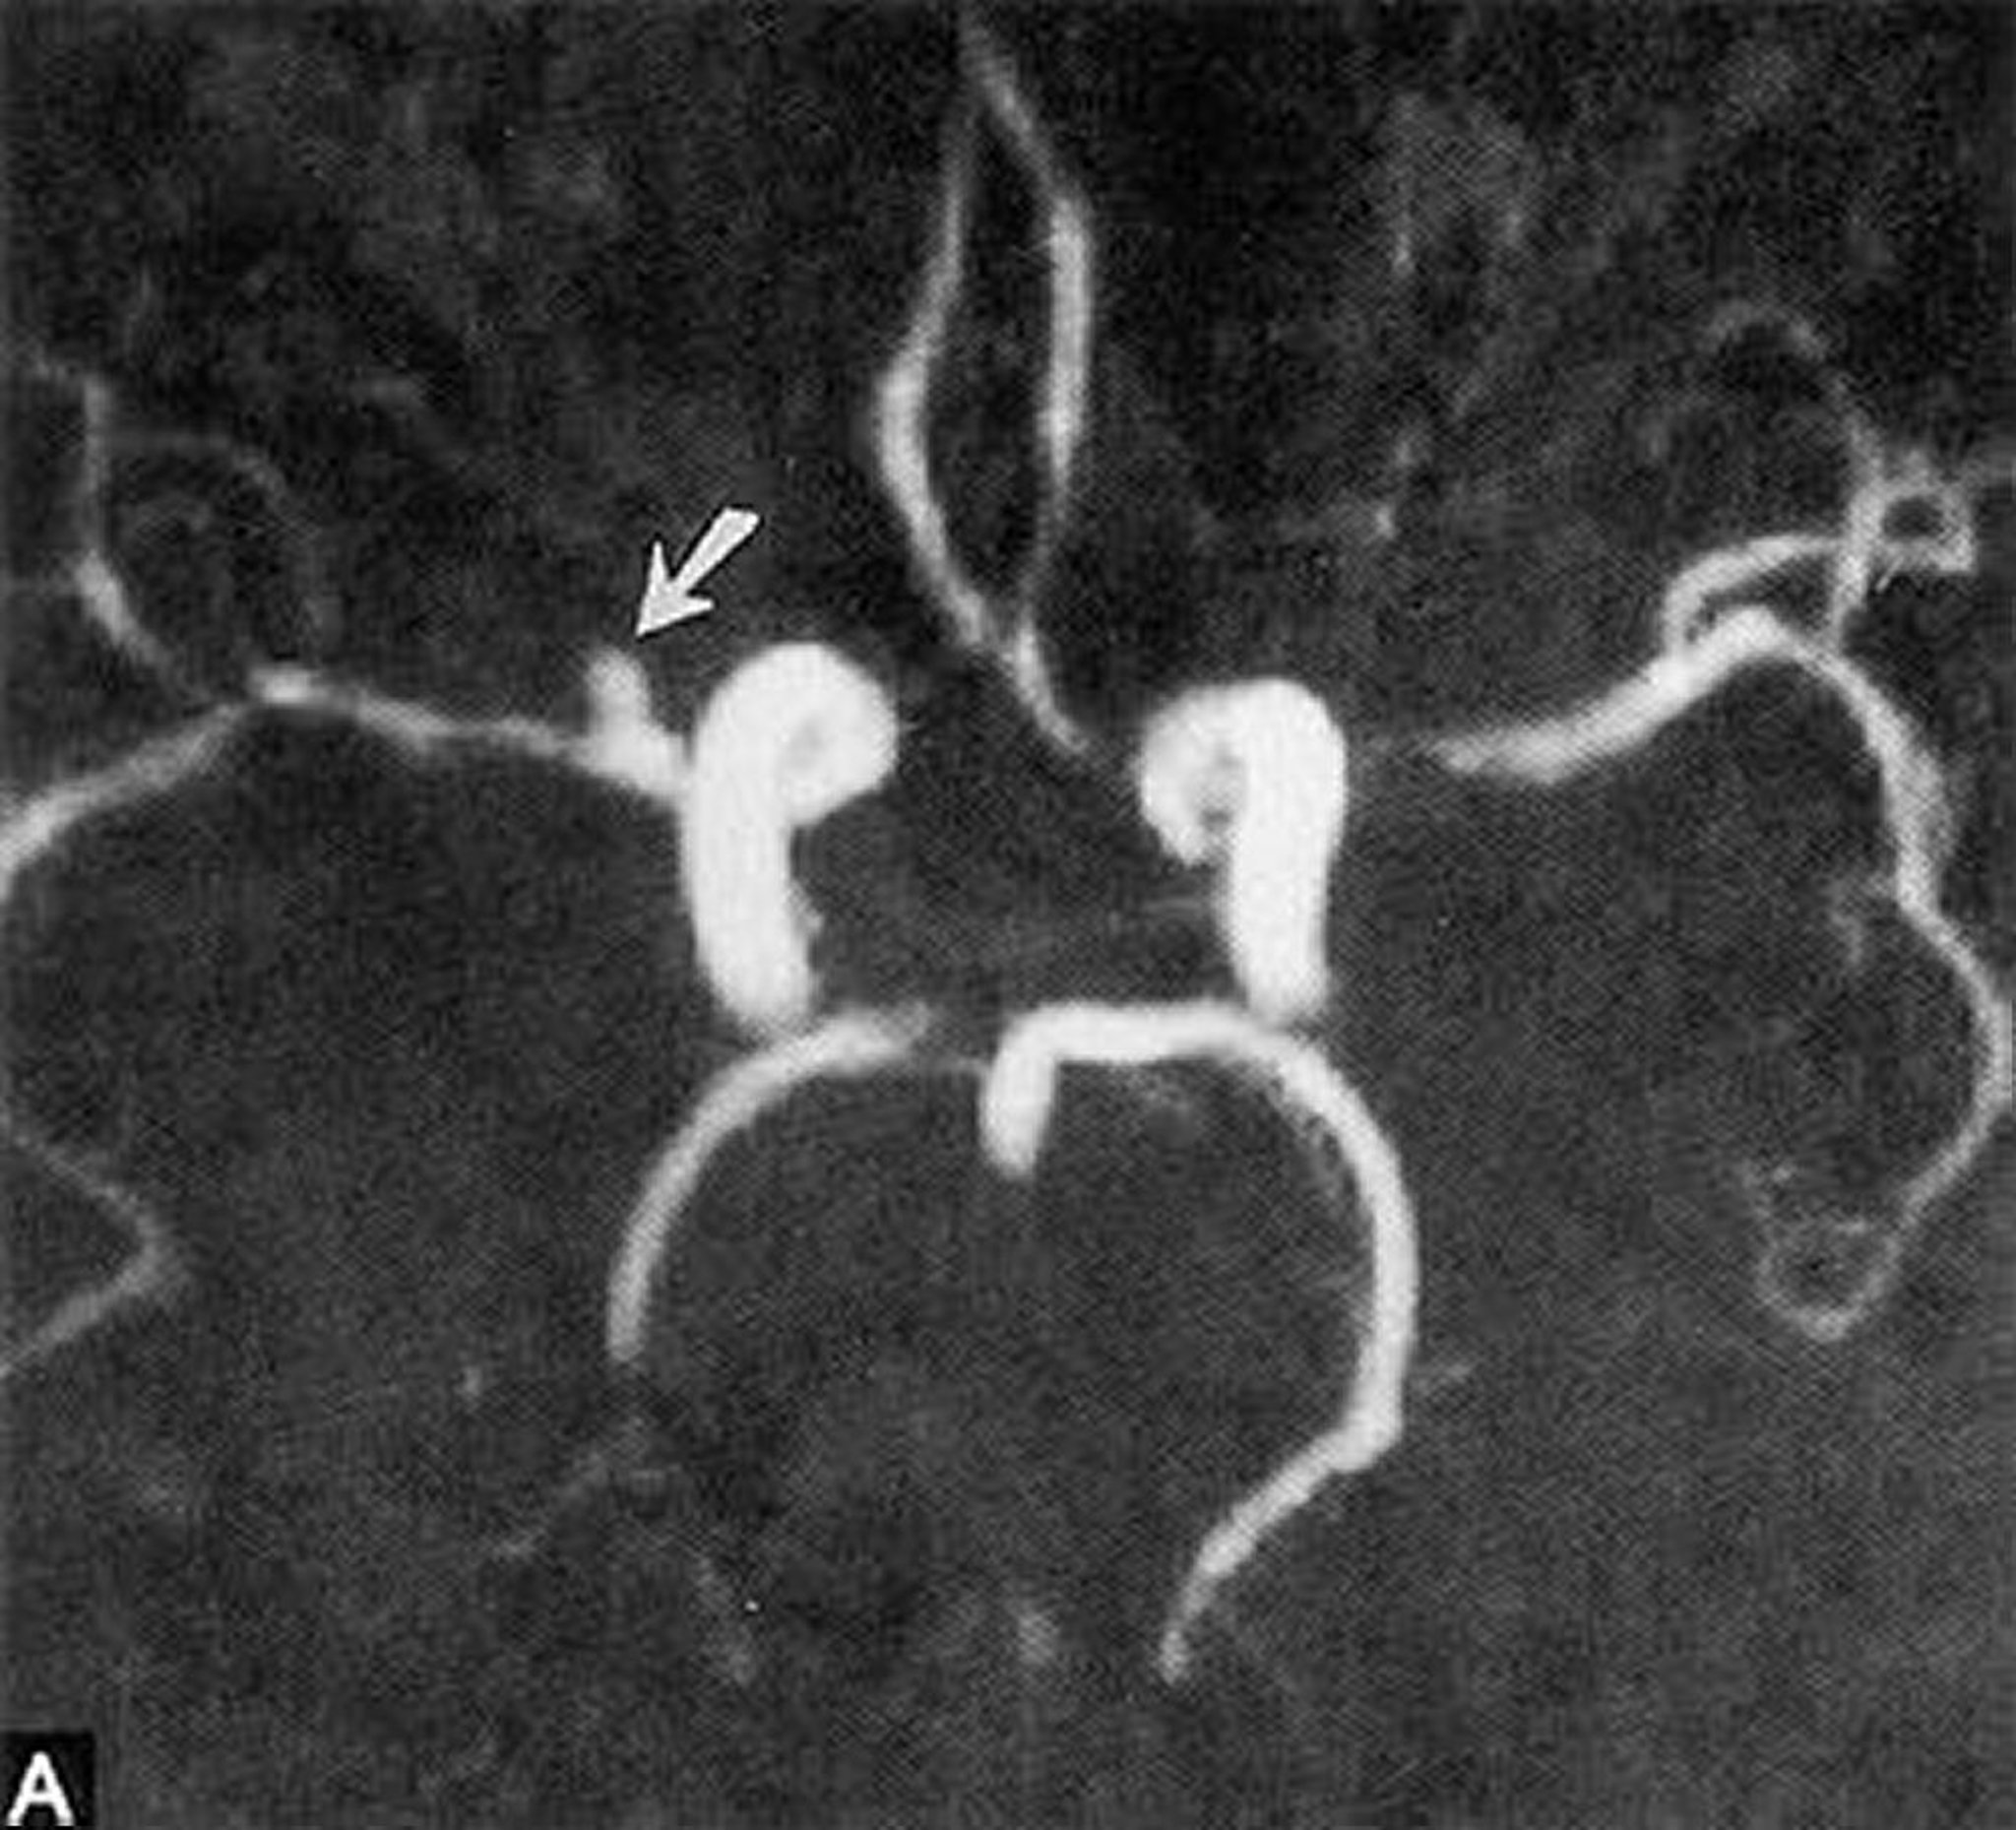

Aneurisma sacular

Esta angiorresonancia muestra un pequeño aneurisma sacular en la porción horizontal de la arteria cerebral media derecha (flecha).

By permission of the publisher. From Ritter A, Hayman L, Charletta D. In Atlas of Cerebrovascular Disease. Edited by PB Gorelick and MA Sloan. Philadelphia, Current Medicine, 1996.